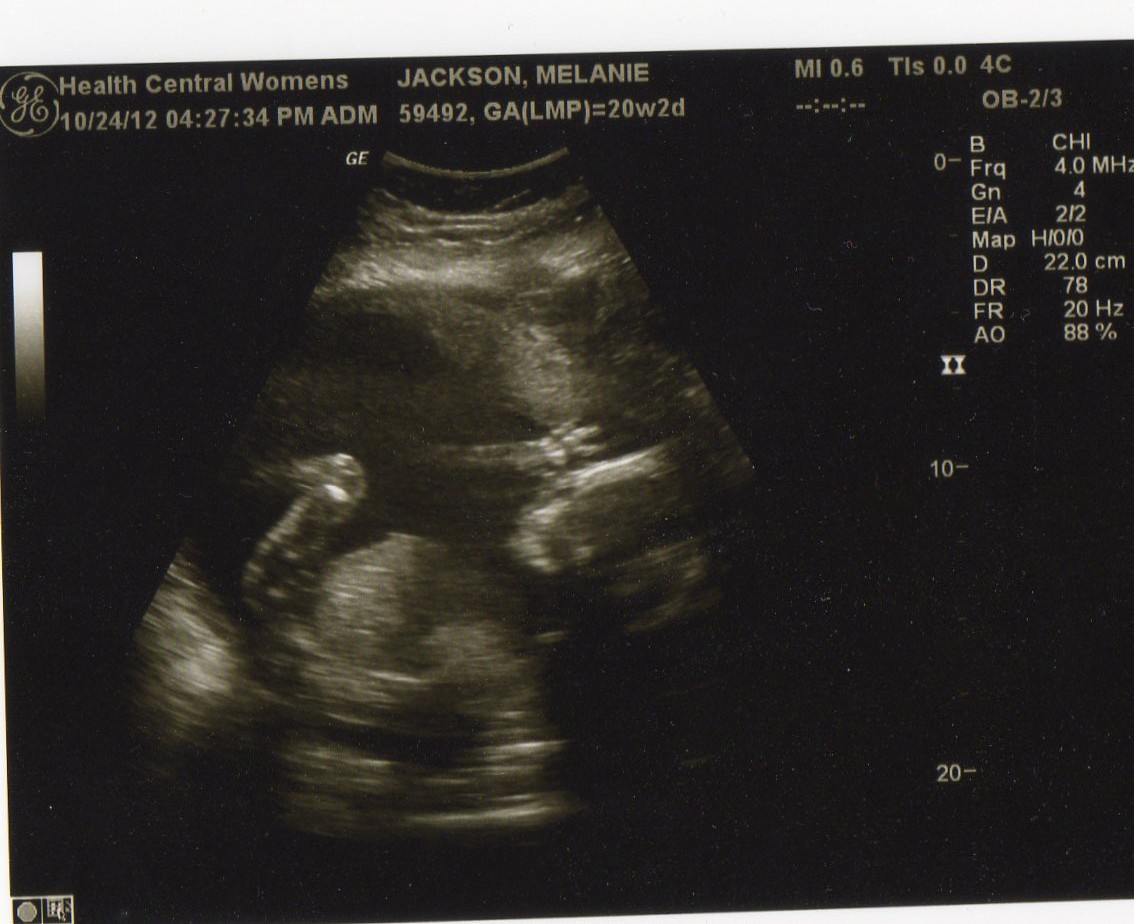

Here are some shots from the sonogram. He measured average in pretty much every category which is what we want. He moved around quite a bit, and I do think this little guy is more of a mover and shaker than Luke was. Luke would find a spot and just sit, but this one I feel a lot more consistently and more often.

| This was our confirmation that it's another boy. |

| The best profile we got of this little guy. He's a mover and a shaker and wouldn't stay still to get anything better. |